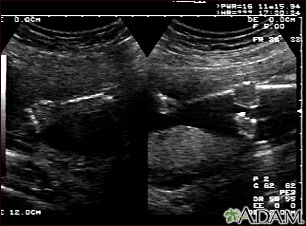

Ultrasound, normal fetus - arms and legs

Ultrasound, normal fetus - arms and legs

This is a normal fetal ultrasound performed at 19 weeks gestation. This is the type of spilt-screen display you might see during an ultrasound, or if the technician prints a copy of the ultrasound for you. This ultrasound shows both the left arm (seen in the left side of the display), and the lower extremities (seen in the right side of the display). The white areas of the arm or legs is developing bone.